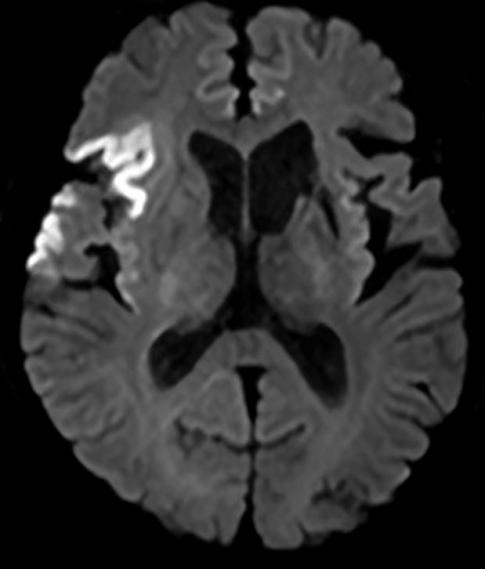

入院查体:神志清,精神一般,言语不清,双侧额纹对称,双侧瞳孔等大等圆,直径2.5 mm,对光反射灵敏,双侧鼻唇沟对称,口角左偏,左侧肢体肌力正常,右侧肢体肌力4级,指鼻试验阴性,生理反射存在,病理反射未引出,美国国立卫生研究院卒中量表NIHSS评分(National Institute of Health stroke scale, NIHSS)2分。入院诊断为急性脑梗死、高血压病3级(极高危)、陈旧性脑梗死。给予以阿司匹林联合氯吡格雷抗血小板,阿托伐他汀降脂稳定斑块,申捷营养神经等对症支持治疗。入院后进行头颅磁共振检查,提示右侧额顶颞叶、岛叶急性脑梗死,双侧大脑前动脉共左干,见图 1。经胸超声心动图提示:左心房增大,二尖瓣、三尖瓣轻度反流。颈动脉超声提示:双侧颈动脉内膜增厚伴左侧斑块形成(狭窄 < 50%)。椎动脉超声提示:声像图及多普勒血流频谱未见异常。自身抗体阴性。发泡试验结果为:强阳性,右向左分流(固有型,4级)。

右侧额顶颞叶、岛叶急性脑梗死 图 1 患者头颅磁共振DWI